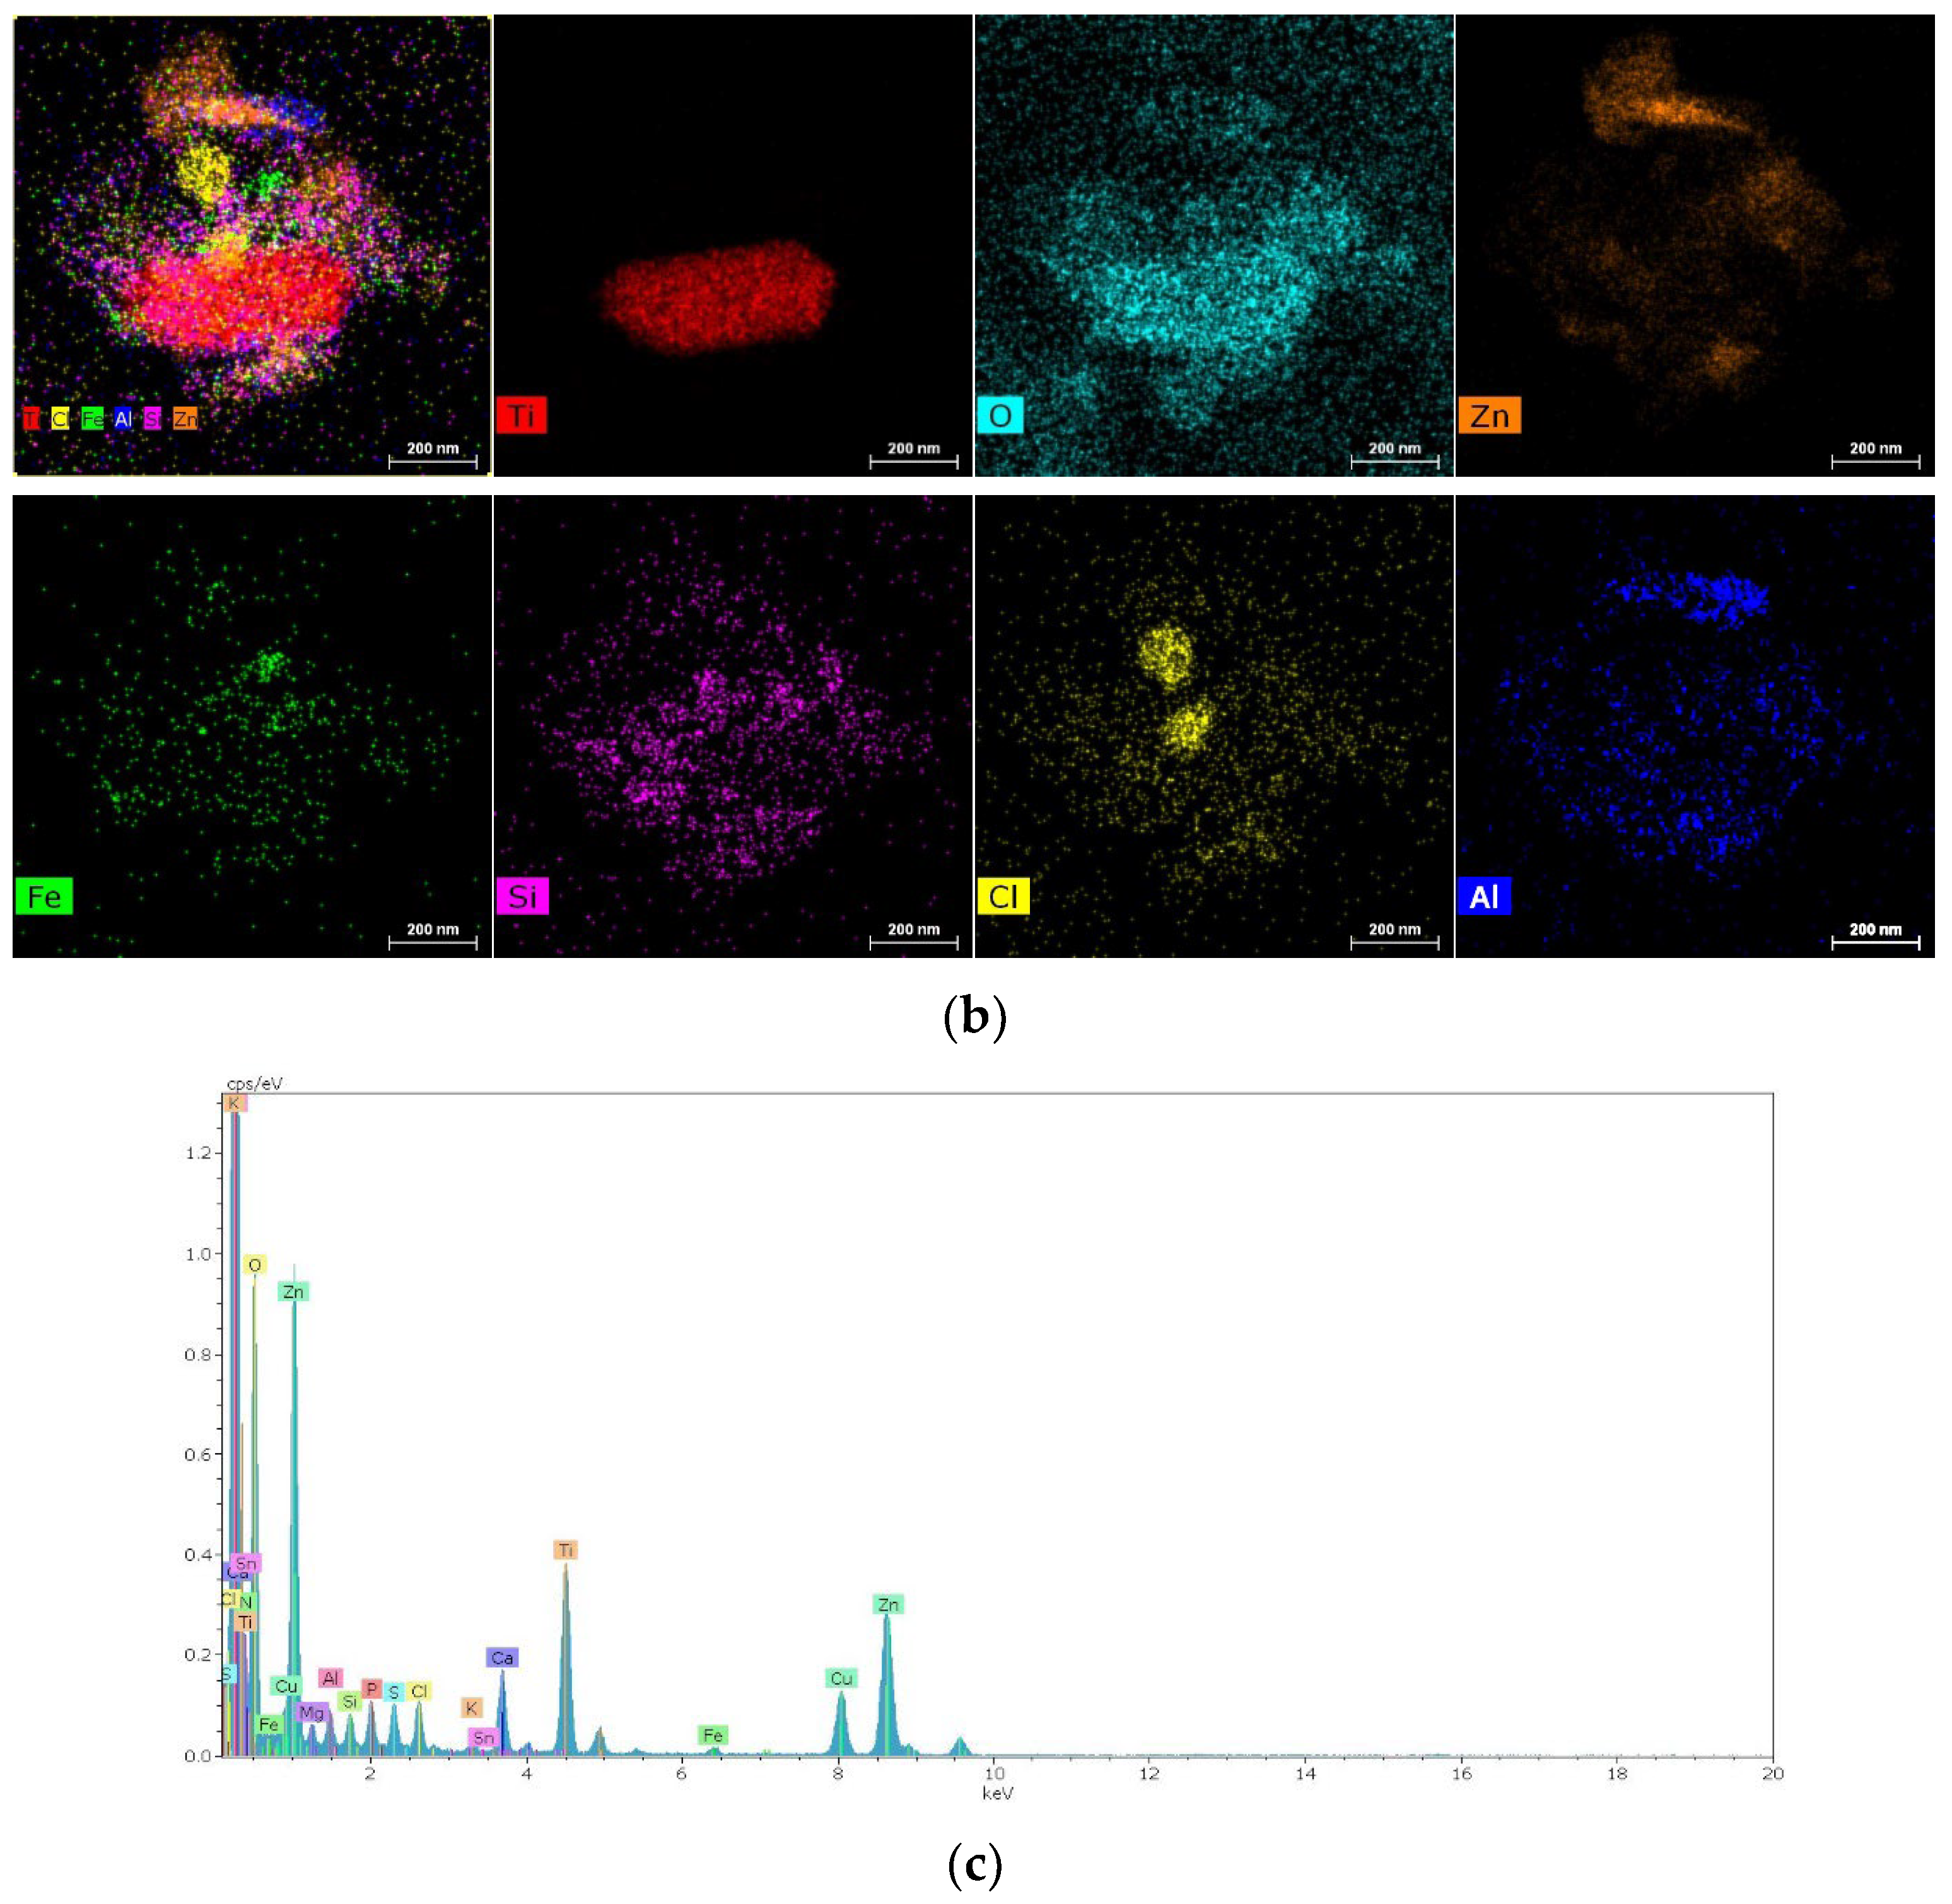

2.1.1. Results of X-ray and Electron Microscopic Studies

4.4. Methods of Scanning Electron Microscopy (SEM) and Transmission Electron Microscopy (TEM) with Energy Dispersive (ED) Analysis